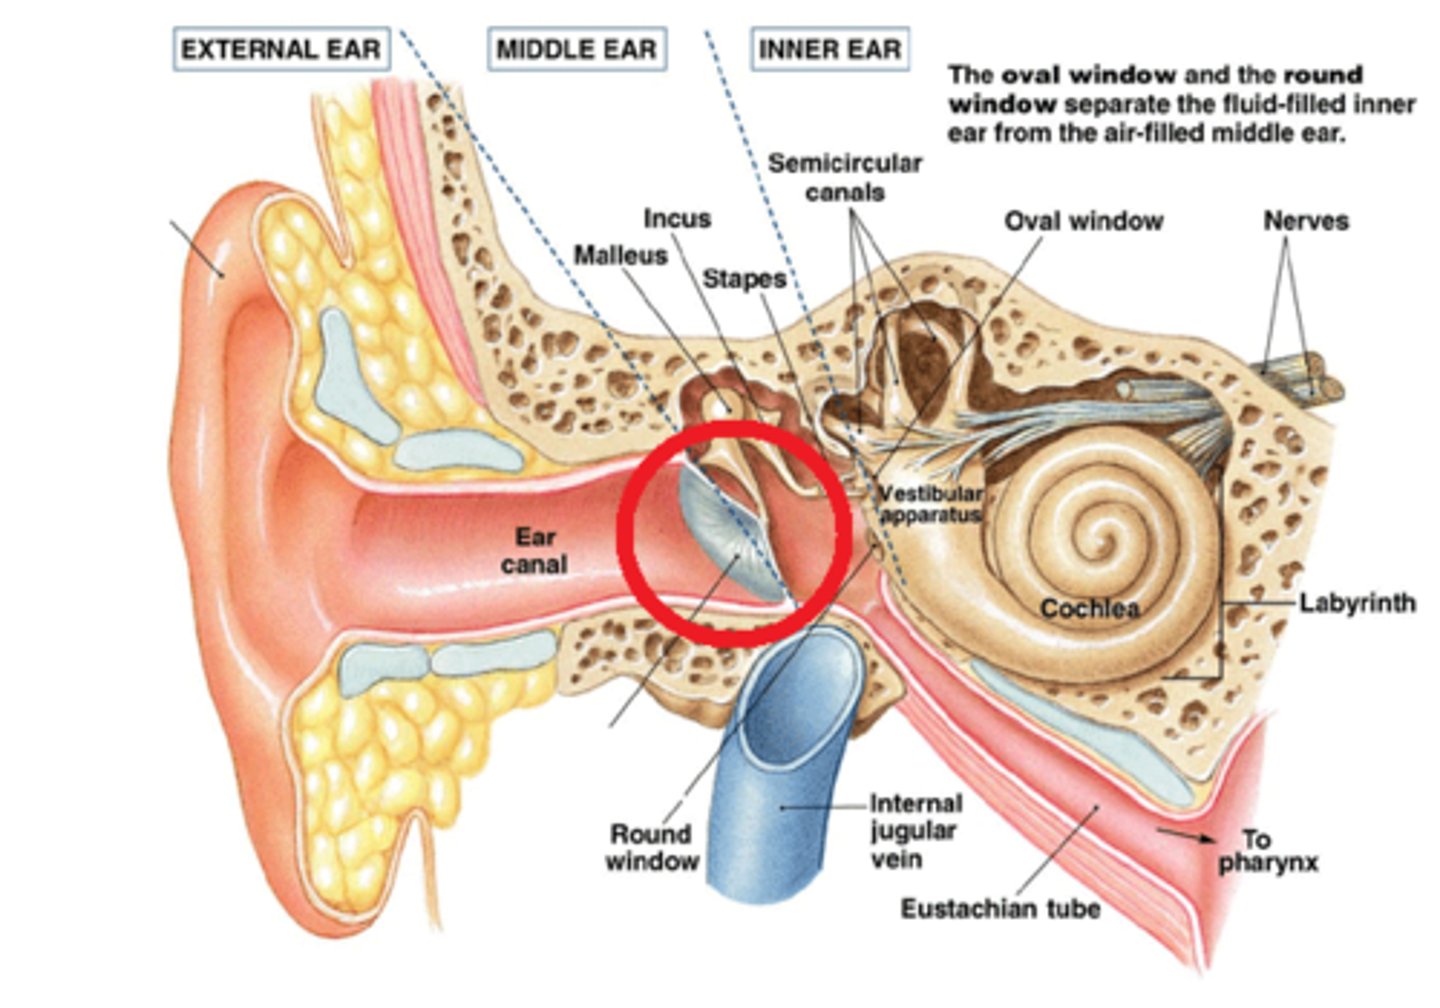

auditory ossicles

EAM

tympanic membrane

tympanic cavity

Eustachian tube

mastoid air cells

coclea

semicircular canals